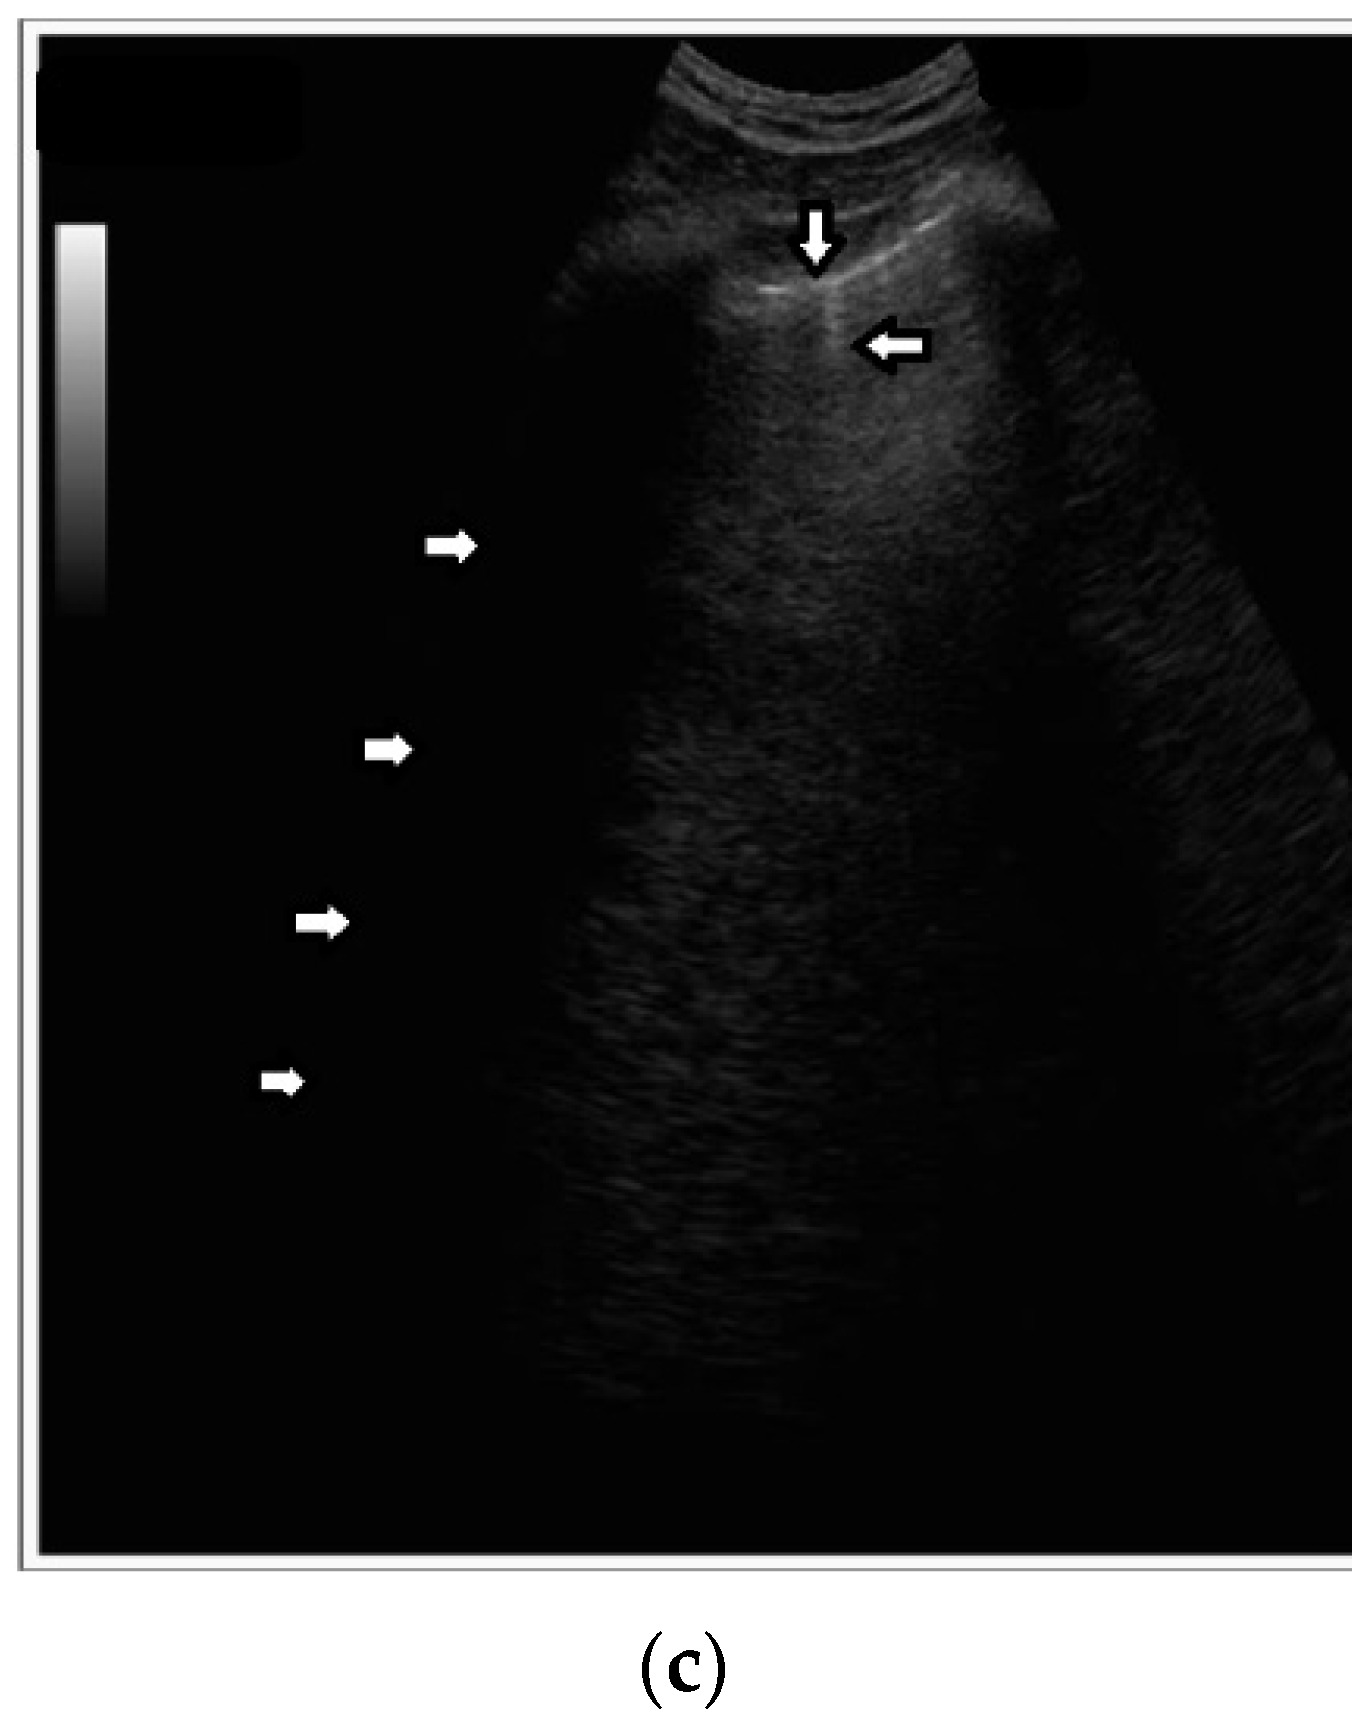

In healthy individuals, an ultrasound examination of the lungs visualizes only the lung surface, termed the pleural line (see Figure 2a). A-line artifacts are visible below the pleural line. These form horizontal lines that appear at regular intervals, equaling the distance between the body surface and the pleural line (see Figure 2b). Under anatomical conditions, it is not possible to visualize lung parenchyma and the interstitium. Only when subpleural areas of the lungs lose their aeration due to lesions can vertical artifacts and/or subpleural consolidations be observed [7]. Why is this so?

Once an US pulse reaches the pleura plane through the chest wall, it is partially reflected toward the probe and partially transmitted to the channels provided by a specific distribution of the aerated spaces, which characterizes the outer lung surface. In a healthy lung, the size of the interalveolar septa is, and reasonably so, supposed to be comparable to a capillary lumen (less than 10 microns), and an US pulse “sees” this aerated space distribution as a compact air wall. In this case, the acoustic energy is essentially reflected back to the probe. The lung surface is highlighted with a thick white line (the so-called pleural line), and A-line artifacts are visible below the pleural line thanks to the multiple reflections of the acoustic wave between the lung surface and the probe. Replicas of the thoracic wall structures are also often well visible between every pair of A lines thanks to the replica and mirror effects as a consequence of the strong reflection of the lung surface. It is worth noting, however, that the affirmation “The A line artifacts form horizontal lines that appear at regular intervals equaling the distance between the body surface and the pleural line” is not entirely correct. Such an affirmation is correct only if the pleural plane is exactly parallel to the head of the probe [8].

On the other hand, in the presence of thickened interstitial spaces, the pulse energy can be partially trapped by the latter. This can subsequently be reradiated toward the probe after multiple reflections between the separated aerated spaces, giving rise to vertical artifacts, which arise from the pleura line. The imaging parameters play a fundamental role in the formation of the artifacts, and the visibility of a vertical artifact (that is, its brightness, lateral dimension, and length) depends on multiple non-orthogonal factors including the gain, the time gain compensation (TGC), and all the parameters that can be easily set by the operator from the scanner keyboard. The clinical information that can be obtained from lung US images is essentially artifactual information except in the case of consolidation when anatomical information is obtained.

Figure 2. (a) Lung ultrasound, linear probe: white stars (*) muscles of the chest wall; down arrow () well-defined pleural line (perpendicular ultrasound beam); left arrow () blurred pleural line secondary to the tangential incidence of the ultrasound beam; up arrow () subcutaneous tissue; right arrow () A line, horizontal artifact. (b) Lung ultrasound, convex probe: down arrow—pleural line, smooth, echoic and regular; left arrow—A-line artifact.